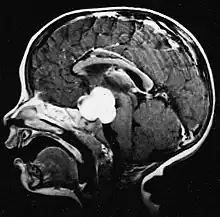

Le médulloblastome est la tumeur cérébrale maligne la plus fréquente chez l'enfant. L'incidence la plus élevée survient chez les enfants âgés de 2 à 7 ans. Le plus grand risque de maladie demeure dans l'enfance, car le médulloblastome est très rare chez les personnes de plus de 21 ans.

Cette tumeur est typique de la fosse postérieure, où elle est localisée dans les deux hémisphères du cervelet ou dans le vermis cérébelleux. Parce qu'il est envahissant et à croissance rapide, il se propage généralement à d'autres parties du système nerveux central (SNC) via le LCR et peut infiltrer le plancher du quatrième ventricule voisin et les méninges. Plus rarement, des métastases supplémentaires du SNC peuvent survenir. Lorsque la tumeur maligne survient, les symptômes comprennent la perte d'équilibre, l'incoordination, la diplopie, la dysarthrie et l'atteinte du quatrième ventricule, ce qui entraîne souvent une hydrocéphalie obstructive, des maux de tête, des nausées et des vomissements et une démarche instable.

L'IRM montre généralement une lésion de contraste massive impliquant le cervelet. Comme mentionné ci-dessus, le médulloblastome a une forte propension à infiltrer localement les leptoméninges ainsi qu'à se propager à travers l'espace sous-arachnoïdien, impliquant les ventricules, la convexité cérébrale et les surfaces leptoméningées de la colonne vertébrale. Par conséquent, il est nécessaire de mettre en résonance tout l'axe crânio-spinal.

Le but de la chirurgie est d'enlever autant que possible la masse présentée par la lésion. En effet, les tumeurs résiduelles postopératoires entraînent un moins bon pronostic. La présence de cellules tumorales dans le liquide céphalo-rachidien ou la détection par résonance de métastases leptoméningées est également un signe avant-coureur d'un pronostic défavorable. La chirurgie seule n'est généralement pas curative. Dans certains cas, cependant, une irradiation thérapeutique de l'axe craniospinal, focalisée sur le site tumoral primaire, peut en résulter. L'ajout d'une chimiothérapie après la radiothérapie augmente le taux de guérison. Des médicaments à base de platine (cisplatine ou carboplatine), de l'étoposide et un agent alkylant (cyclophosphamide ou lomustine) sont utilisés avec la vincristine. Avec un traitement approprié, les cas de longue survie de plus de 3 ans chez les patients atteints de médulloblastome varient de 60 à 60 ans et 80 Pour cent.